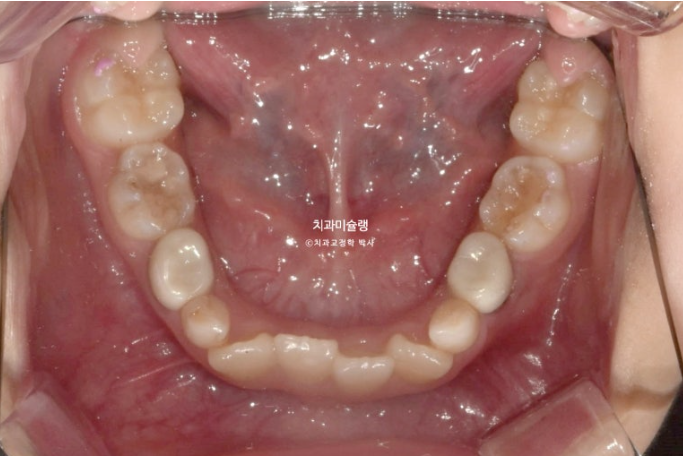

23년 10월, 교정치료를 위해 온 어린이 입니다.

앞니 두 개 높낮이 차이, 앞니가 깊게 물리는 과개교합이 보입니다.

앞니 네개 중 옆 앞니 즉 측절치가 나올 공간이 좁습니다.

아래도 마찬가지 입니다.

앞니가 벌써 삐뚤삐뚤 합니다.

송곳니가 나올때는 어떻게 될까요?

덧니 100% 예약입니다.